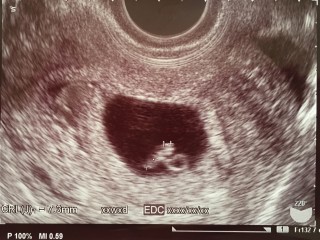

2回目の検診で無事心拍確認。でも子宮内出血があるようで、母子手帳はまだ…赤ちゃんの大きさもまだ小さいみたいで、止血剤と流産予防の薬をもらいまた2週間後にいきます。無事に育ってくれますように>_<